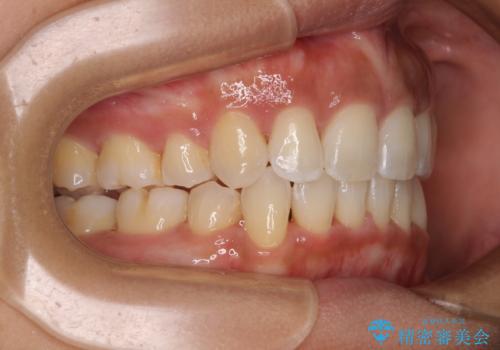

- 下唇が突き出るような口元の突出感が気になるとのことで来院された患者様です。

上下顎ともに前突した歯列であったので、上下ともに左右の第1小臼歯4本を抜歯し、ワイヤー装置にて矯正治療を行うこととしました。

抜歯スペースに前歯を移動させることで歯の突出感が改善され、非常に唇が閉じやすい仕上がりとなりました。